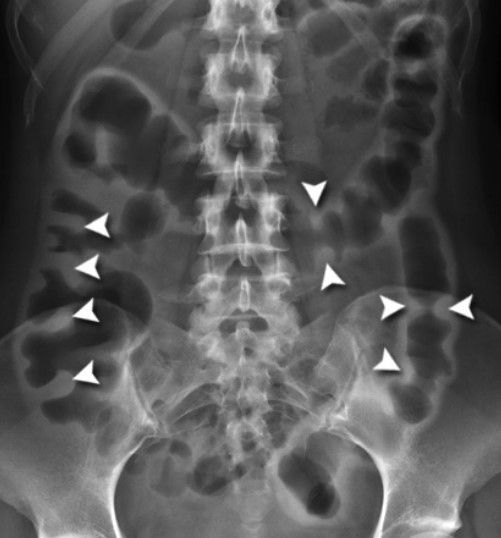

What feature is this and which IBD is it more common in?

Thumbprinting

UC due to thickening of colon